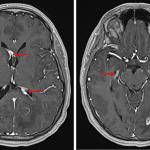

Neurosarcoidosis